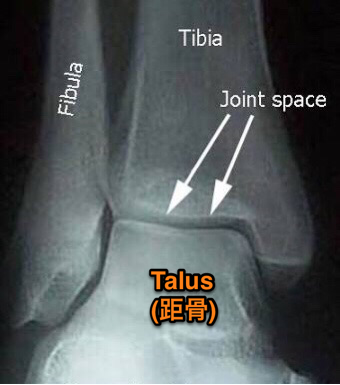

足首がかたい

足首がかたい

カイロプラクティックは背骨や骨盤だけではありません。

カイロプラクティックは背骨や骨盤だけではありません。